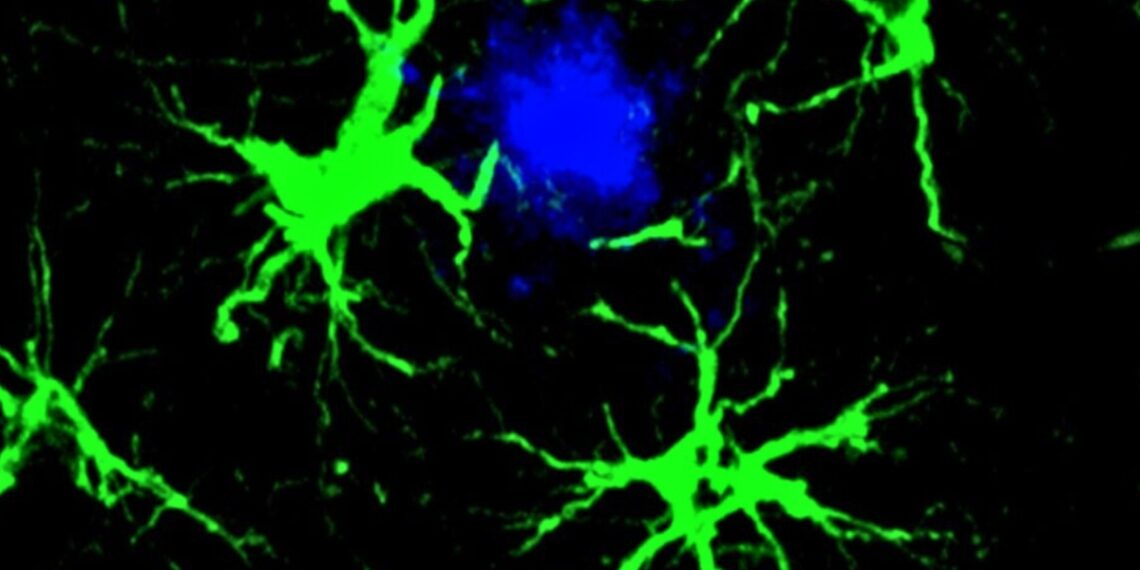

Šiame tyrime mokslininkai sutelkė dėmesį į žvaigždiškos formos smegenų ląsteles – astrocitus. Jie buvo genetiškai modifikuoti taip, kad atpažintų ir šalintų su kognityviniu nuosmukiu bei Alzheimerio liga siejamus amiloido beta baltymus.

Įprastai astrocitai atlieka daug svarbių užduočių smegenyse, įskaitant „tvarkdarių“ funkcijas. Ši technologija leidžia sutelkti jų bendrą galią ir nukreipti ją prieš amiloido beta baltymus.

Gavę naują „užduotį“, astrocitai tampa itin susitelkę į amiloido beta apnašų šalinimą ir tai atlieka labai efektyviai.